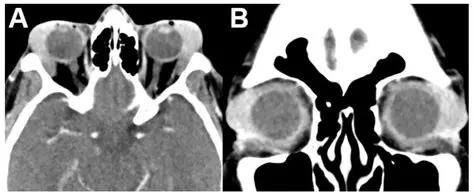

Understanding Orbital Tumors